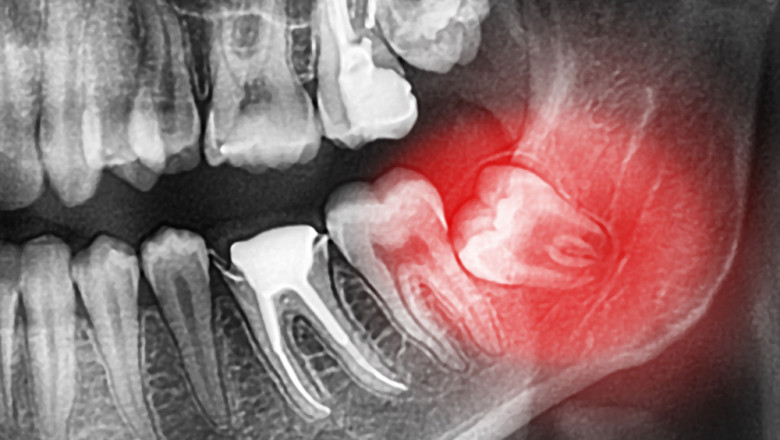

Dental Clinic Oral Surgery Sedation kwcdental 488 views Are you looking for oral surgery sedation? Visit https://www.kwcdental.com. At KWC Dental, for all surgical procedures, patients may discuss sedation options with a dentist. For more details, visit site. oral surgery sedation Comments Comment 0 comment Best Oldest Newest Write the first comment for this!